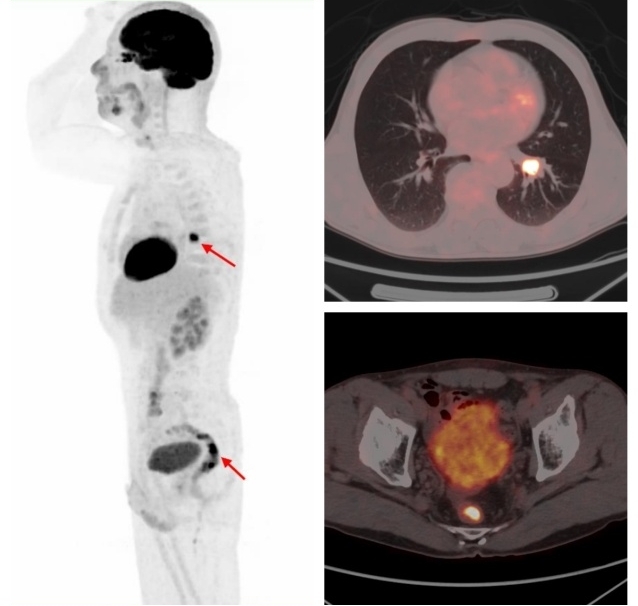

原發(fā)肺鱗癌合并直腸腺癌